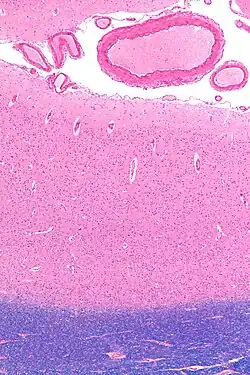

Tissue slice from the brain of an adult macaque monkey. The cerebral cortex is depicted in dark violet.